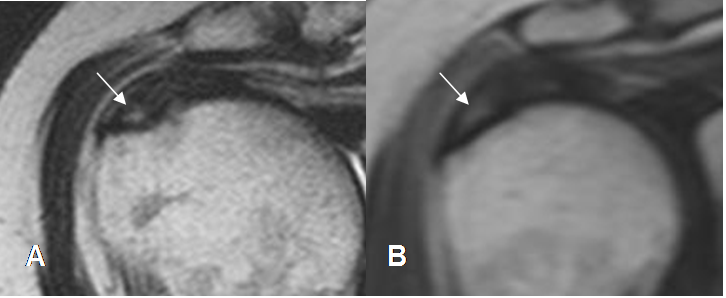

Fig 116. Ruptura parcial del supraespinoso.

A: RM coronal en T2 y B: RM coronal en STIR. Ruptura parcial del tendón supraespinoso hacia la superficie humeral (Flechas delgadas), con fibras íntegras en la superficie bursal. (Flechas gruesas).

Fig 117. Ruptura parcial del supraespinoso.

A: RM coronal en T2 y B: RM coronal en STIR. Ruptura parcial del tendón supraespinoso hacia la superficie bursal (Flechas delgadas), con fibras íntegras en la superficie humeral. (Flechas gruesas).